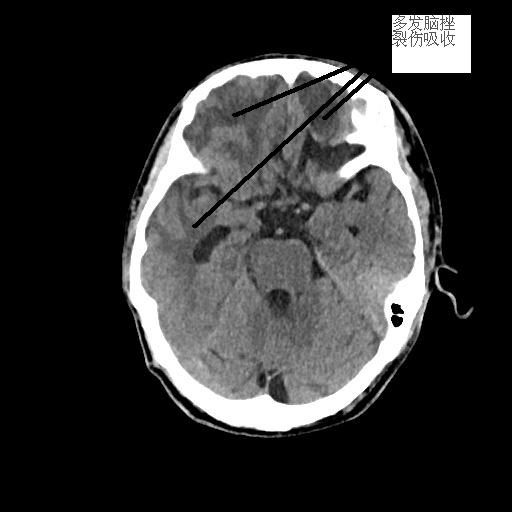

患者潘先生,因騎車摔倒入院搶救。入院時(shí),潘先生神志已模糊,無法對(duì)答,檢查檢驗(yàn)提示顱內(nèi)多發(fā)損傷,出現(xiàn)腦疝,病情危重,我院神經(jīng)外科團(tuán)隊(duì)緊急聯(lián)系福醫(yī)大附二院當(dāng)日值班專家來院開展開顱手術(shù)。經(jīng)及時(shí)搶救,患者病情穩(wěn)定,轉(zhuǎn)危為安。

<<<< 治療前后對(duì)比